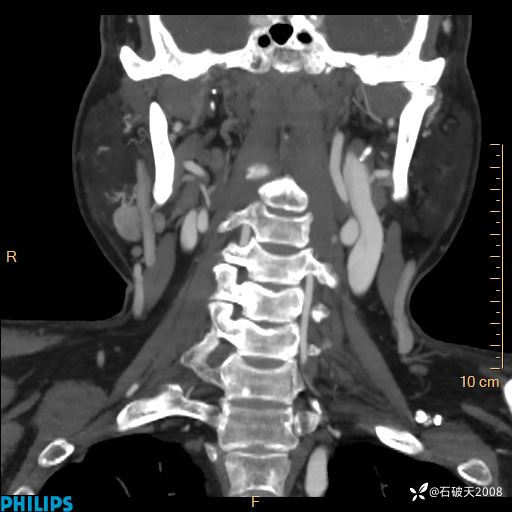

动脉期